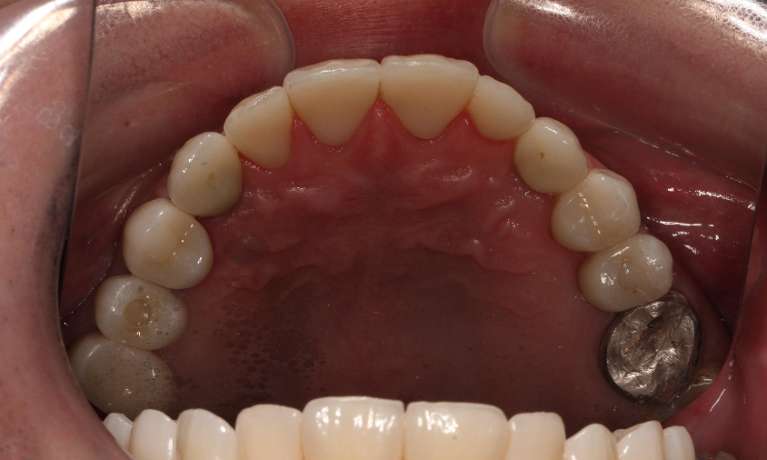

This man in his 50s was unhappy with the amalgam filling used to fix cavities. After discussing options, we agreed to fix his appearance by putting crowns on the teeth which create more of a natural look. This patient was very happy with the end result and is now in maintenance mode.